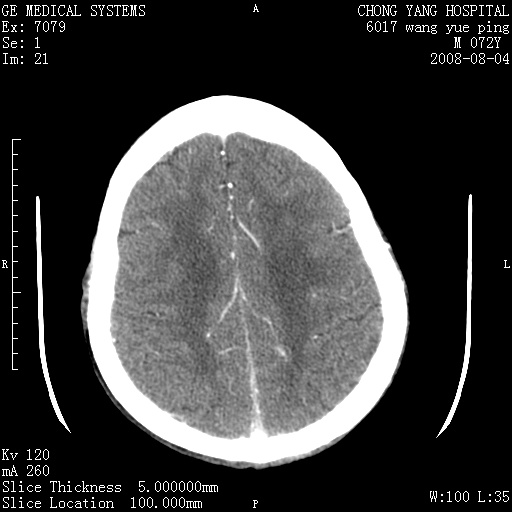

标题: CT14987:M72Y,头痛头昏,BP220/110. [打印本页]

标题: CT14987:M72Y,头痛头昏,BP220/110.

1)考虑左侧小脑脑梗塞。2)脑白质病。3)脑萎缩。4)双侧鼻腔新生物(息肉?)并阻塞性副鼻窦炎。

1.左侧小脑大面积梗塞;2.左侧基底节区腔梗;3.白质疏松;4.脑萎缩;5.慢性副鼻窦炎

小脑左侧病灶呈扇形分布,增强后未见明显瘤体样节结影,病变区未见强化。

支持:左侧小脑脑梗塞梗塞表现

另:脑白质病。脑萎缩。双侧鼻腔新生物(息肉?)并阻塞性副鼻窦炎。

1)考虑左侧小脑脑梗塞,建议治疗后复查除外其他,左基底节区腔隙性脑梗塞2)脑白质变性3)脑萎缩。4)双侧鼻腔新生物(息肉?)并阻塞性副鼻窦炎。